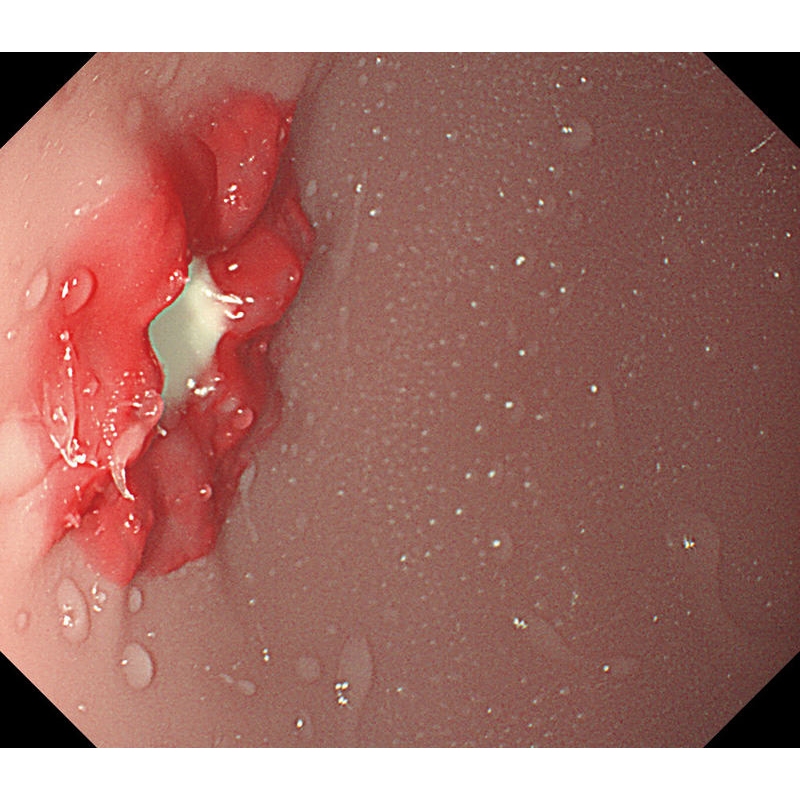

- V želodcu je mogoče opazovati želodčno razjedo in zgodnji rak želodca. Za opazovanje je mogoče pritrditi tudi štiri vrste polipov po Yamadovi klasifikaciji tipov od I do IV.

- V dvanajstniku je mogoče reproducirati razjedo.